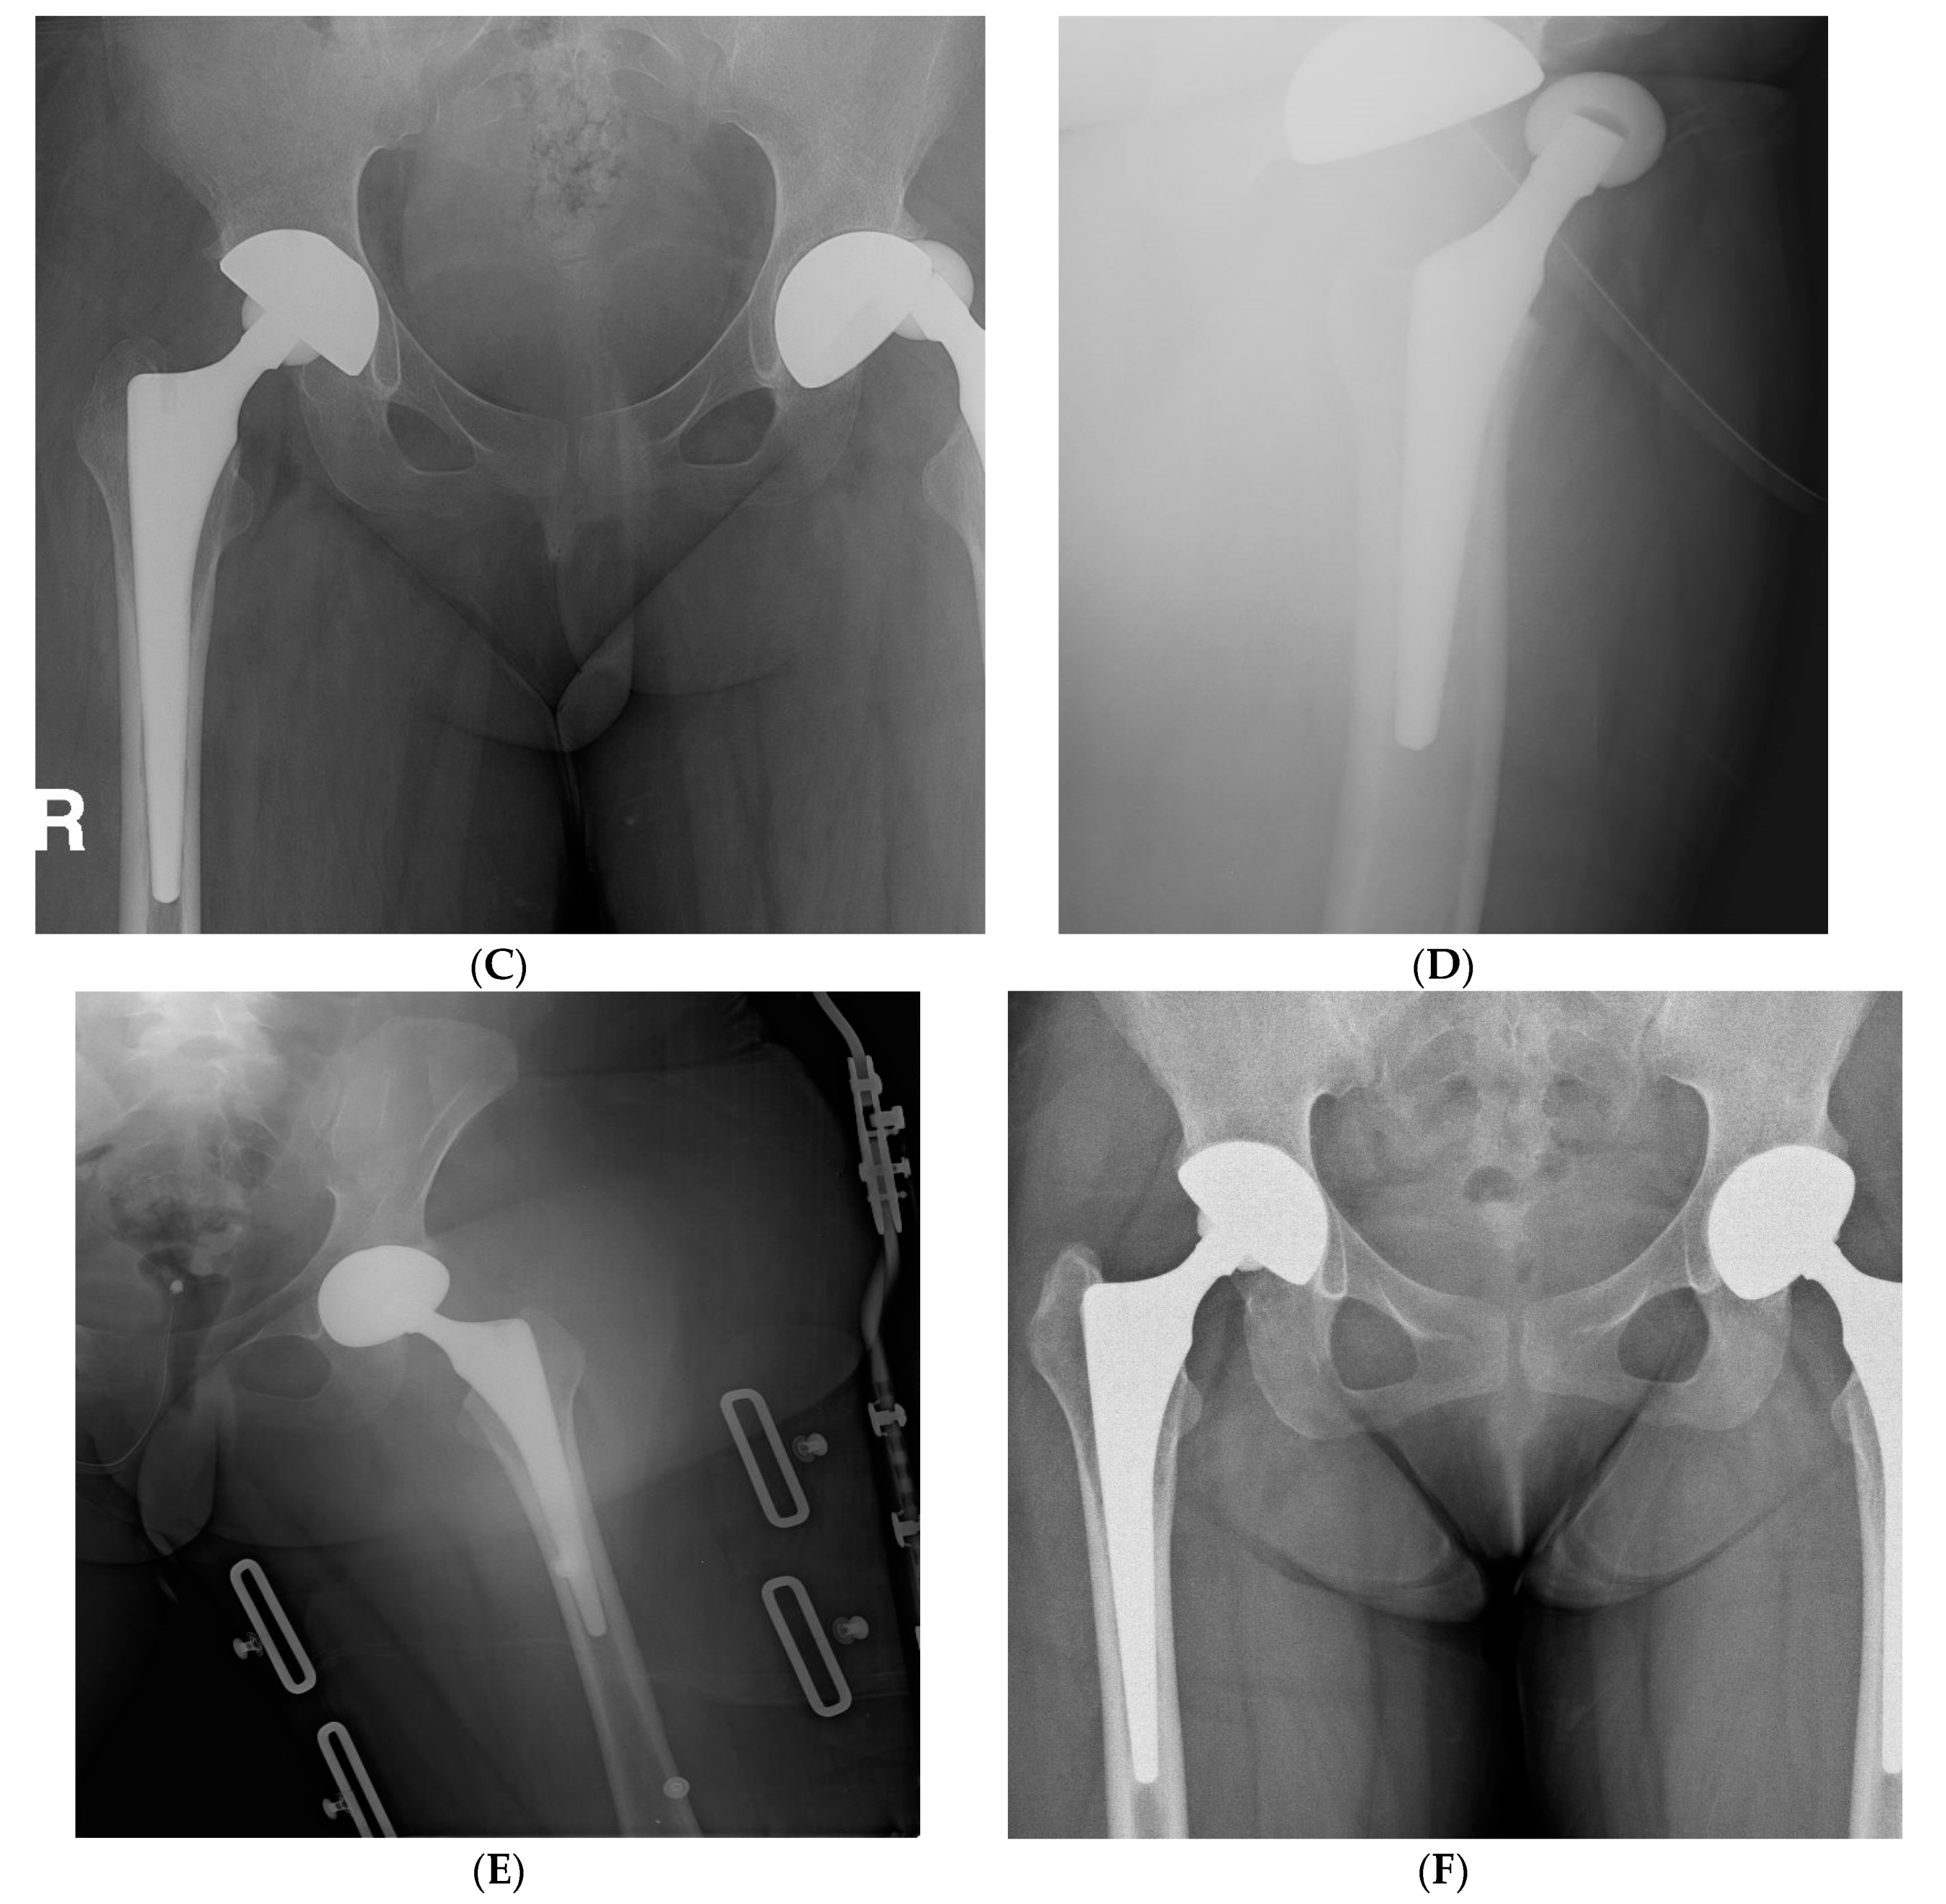

Figure 2.

(A,B) Preoperative and postoperative hip radiographs of a 33-year-old woman with cognitive dysfunction and visual disturbance after removal of recurrent craniopharyngioma. She underwent simultaneous bilateral THA due to ONFH. (C,D) Radiographs of the same woman on the 15th postoperative day, when she visited the emergency department due to severe pain in the left hip. Anteroposterior and lateral images demonstrated anterior hip dislocation. (E) Hip radiograph after performing closed reduction followed by abduction brace application under general anesthesia. (F) Eight-year postoperative radiograph showed stable implant fixations.

The rates of the appearance of radiolucent lines in radiographs around the acetabular cup were 5.9% and 4.4% in the brain tumor and control groups, respectively (P-value = 1.000); they were 8.8% and 5.9% around the femoral stem (P-value = 0.683) (Table 6). There was no complete radiolucency in either group, suggesting acetabular loosening. All femoral radiolucent lines were confined to one or two zones. More HO was observed in patients with brain tumors compared to in the controls (32.4% and 10.3%, respectively; P-value = 0.006), all of which were classified as Brooker grade 1 or 2 (Figure 3).

Figure 3.

(A) Preoperative hip radiograph of a 41-year-old man who had undergone surgical removal of meningioma in the right frontal lobe 4 years prior to THA, demonstrating collapsed osteonecrosis of the right femoral head. (B) Five-year postoperative radiograph demonstrating stable implants with Brooker grade 2 heterotopic ossification. The patient had no pain and was satisfied with the outcome.